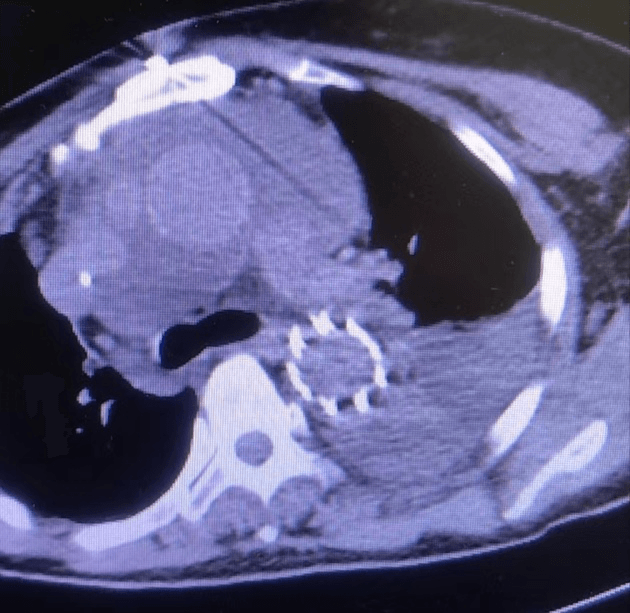

近日,我院急診科會(huì)診來了一位60歲女性患者,患者訴胸背部疼痛4小時(shí)余,疼痛劇烈,不能忍受,來院時(shí)血壓260/135mmHg,于當(dāng)?shù)乜h醫(yī)院行大血管CTA檢查,提示主動(dòng)脈夾層。新型冠狀病毒感染未完全康復(fù)的值班醫(yī)生一路小跑都?xì)獯跤跚巴痹\科會(huì)診,一邊咳嗽一邊問診,由于患者病情危急,請(qǐng)示心外科武小剛科主任后分析:患者系主動(dòng)脈夾層動(dòng)脈瘤(A型),降主動(dòng)脈近段可見明顯破口,升主動(dòng)脈明顯增寬,根據(jù)超聲提示,目前考慮升主動(dòng)脈已有新的破口,需急診行外科手術(shù)治療。與家屬溝通后積極降壓、止痛、備血等,進(jìn)入夾層綠色通道,經(jīng)過快速的術(shù)前準(zhǔn)備,患者及早進(jìn)入手術(shù)室,術(shù)中仔細(xì)剝離血管及周圍組織,小心翼翼的分離出受累血管,嚴(yán)格控制血壓,避免因血壓過高導(dǎo)致血管破裂,建立體外循環(huán)術(shù)中探查升主動(dòng)脈可見1cm破口,驗(yàn)證了術(shù)前的判斷;剪除掉破損血管,植入人工血管,仔細(xì)吻合每一根血管,既不能讓吻合口過小導(dǎo)致血液供應(yīng)不足,也不能讓吻合口出血,一臺(tái)“升主動(dòng)脈置換+全弓置換+象鼻術(shù)”需要經(jīng)過長(zhǎng)達(dá)6~8小時(shí)高精度操作,對(duì)醫(yī)生的耐力和精神都是一種考驗(yàn),經(jīng)過6小時(shí)的手術(shù),順利拆除“炸彈”。主刀醫(yī)師從手術(shù)室出來,已經(jīng)是凌晨2點(diǎn)鐘,脫掉早已被汗水浸透的手術(shù)衣,癱軟的坐在椅子上,但患者轉(zhuǎn)危為安,再大的疲憊都是值得的。

術(shù)后復(fù)查恢復(fù)良好